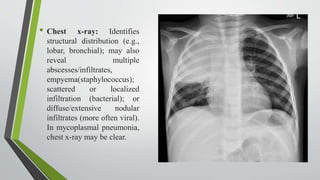

• Chest x-ray: Identifies

structural distribution (e.g.,

lobar, bronchial); may also

reveal multiple

abscesses/infiltrates,

empyema(staphylococcus);

scattered or localized

infiltration (bacterial); or

diffuse/extensive nodular

infiltrates (more often viral).

In mycoplasmal pneumonia,

chest x-ray may be clear.

. • Chest x-ray:Identifies structural distribution (e.g., lobar, bronchial); may also reveal multiple abscesses/infiltrates, empyema(staphylococcus); scattered or localized infiltration (bacterial); or diffuse/extensive nodular infiltrates (more often viral). In mycoplasmal pneumonia, chest x-ray may be clear.